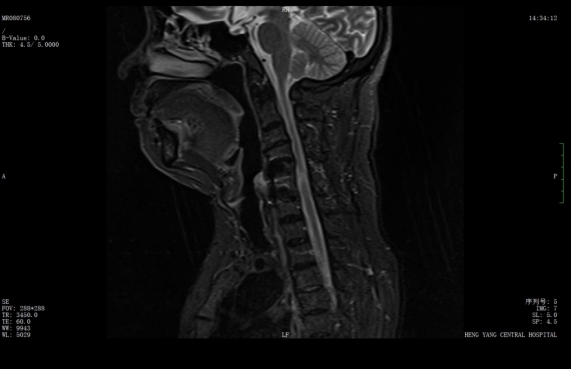

該患者此前因膽囊結(jié)石祁東縣人民醫(yī)院治療,來自衡陽市中心醫(yī)院駐該院副院長(zhǎng)李攀峰為其主刀進(jìn)行手術(shù),術(shù)后患者恢復(fù)良好。后因突發(fā)四肢癱瘓、生活無法自理,為尋求進(jìn)一步治療,經(jīng)醫(yī)聯(lián)體通道轉(zhuǎn)入衡陽市中心醫(yī)院。脊柱外科錢軍博士團(tuán)隊(duì)接診后,迅速組織詳細(xì)問診、體格檢查及系統(tǒng)術(shù)前評(píng)估。查體顯示患者四肢關(guān)鍵肌肌力僅I級(jí),感覺功能明顯減退,結(jié)合影像學(xué)結(jié)果,診斷為頸脊髓損傷伴不全癱,有明確手術(shù)指征。

術(shù)前核磁共振提示:頸椎椎管狹窄、頸脊髓信號(hào)改變